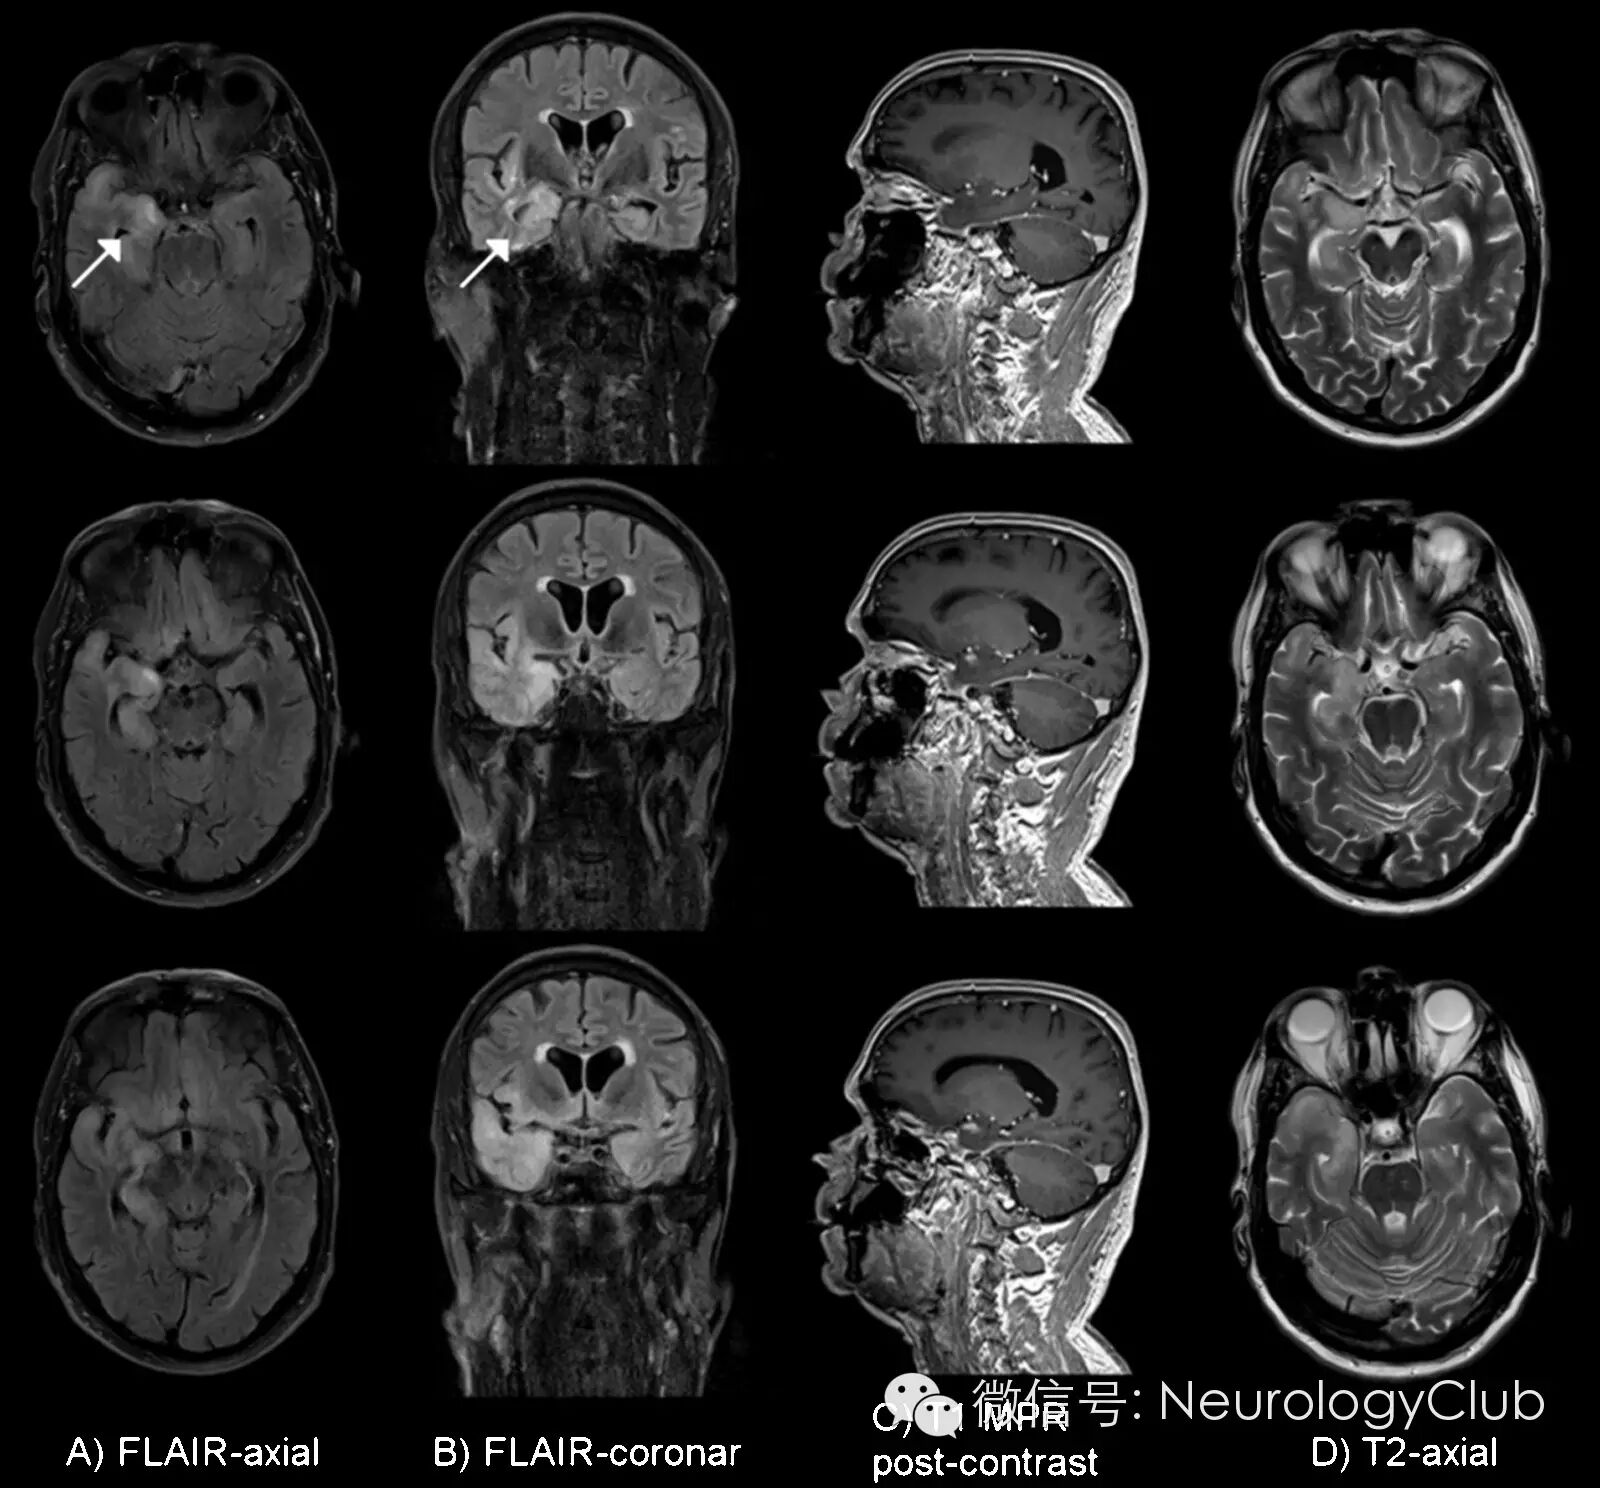

头颅MRI提示两侧颞叶内侧面及海马FLAIR高信号,右侧明显(图)。脑脊液细胞数增多(129/μl),蛋白含量升高(84mg/dl)。血清和脑脊液梅毒ELISA筛查和FTA-IgG阳性,FTA-IgM阴性(血清VDRL检测阳性,鞘内梅毒螺旋体抗体指数107)。疱疹病毒(HSV, VZV, CMV, EBV)血清IgM和脑脊液PCR阴性,伯氏疏螺旋体血清学检测阴性,HIV(HIV-1/HIV-2抗体和p24抗原)以及肝炎系列(HBV和HCV)阴性。毒物学筛查无殊。血清副肿瘤相关抗体(抗Hu,Yo,Ri,Ma/Ta,CV-2,Amphiphysin)和脑脊液自身免疫性脑炎抗体(抗NMDAR,AMPAR,GABA(B)R,LGI1,CASPR2,甘氨酸受体)等亦为阴性。

(入院5天后的3T MRI提示两侧颞叶内侧面及海马异常信号,右侧明显)

患者如此的影像学表现最常见于边缘叶脑炎或单纯疱疹病毒性脑炎,而神经梅毒出现类似MRI改变的少见,容易误诊。近年来,自身免疫性脑炎的研究方兴未艾。其也可出现颞叶内侧面及海马异常信号。本例患者相关自身抗体检测阴性,病毒血清学或PCR无感染依据。可排除上述诊断。